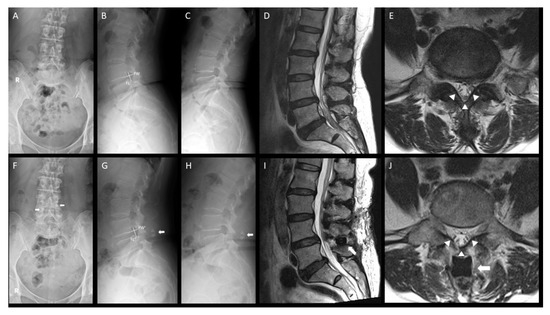

3.5. Illustrative Case